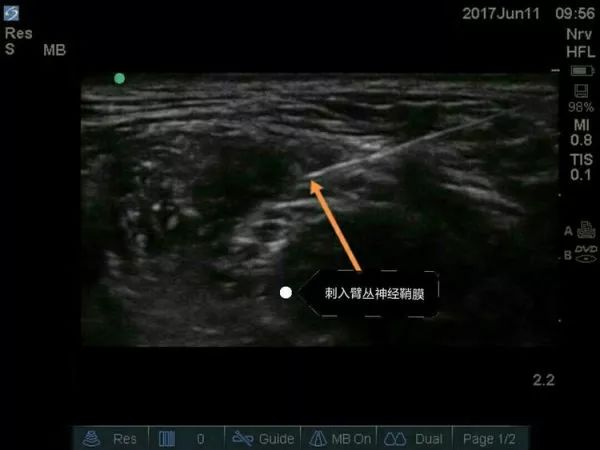

超声引导穿刺针刺入臂丛神经外膜